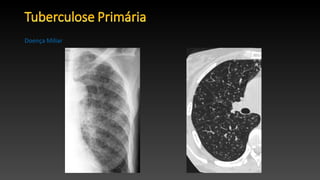

• Doença Miliar afeta entre 1% e 7% dos pacientes de todas as formas de tuberculose.

• É geralmente visto em idosos, crianças e imunodeprimidos.

• A radiografia de tórax é geralmente normal no início do aparecimento dos sintomas.

• Os achados radiográficos clássicos caracterizam-se por distribuição uniforme e difusa

de pequenos nódulos de 2-3 mm, com uma ligeira predominância no lobo inferior, são

vistas em 85% dos casos.

• A TC de alta resolução é mais sensível do que a radiografia convencional,

com nódulos observados em uma distribuição aleatória.

• Os nódulos geralmente desaparecem dentro de 2-6 meses com o tratamento, sem

cicatrizes ou calcificação, no entanto, eles podem coalescer de forma focal ou difusa.

Doença Miliar

• Doença Miliarafeta entre 1% e 7% dos pacientes de todas as formas de tuberculose. • É geralmente visto em idosos, crianças e imunodeprimidos. • A radiografia de tórax é geralmente normal no início do aparecimento dos sintomas. • Os achados radiográficos clássicos caracterizam-se por distribuição uniforme e difusa de pequenos nódulos de 2-3 mm, com uma ligeira predominância no lobo inferior, são vistas em 85% dos casos. • A TC de alta resolução é mais sensível do que a radiografia convencional, com nódulos observados em uma distribuição aleatória. • Os nódulos geralmente desaparecem dentro de 2-6 meses com o tratamento, sem cicatrizes ou calcificação, no entanto, eles podem coalescer de forma focal ou difusa. Doença Miliar